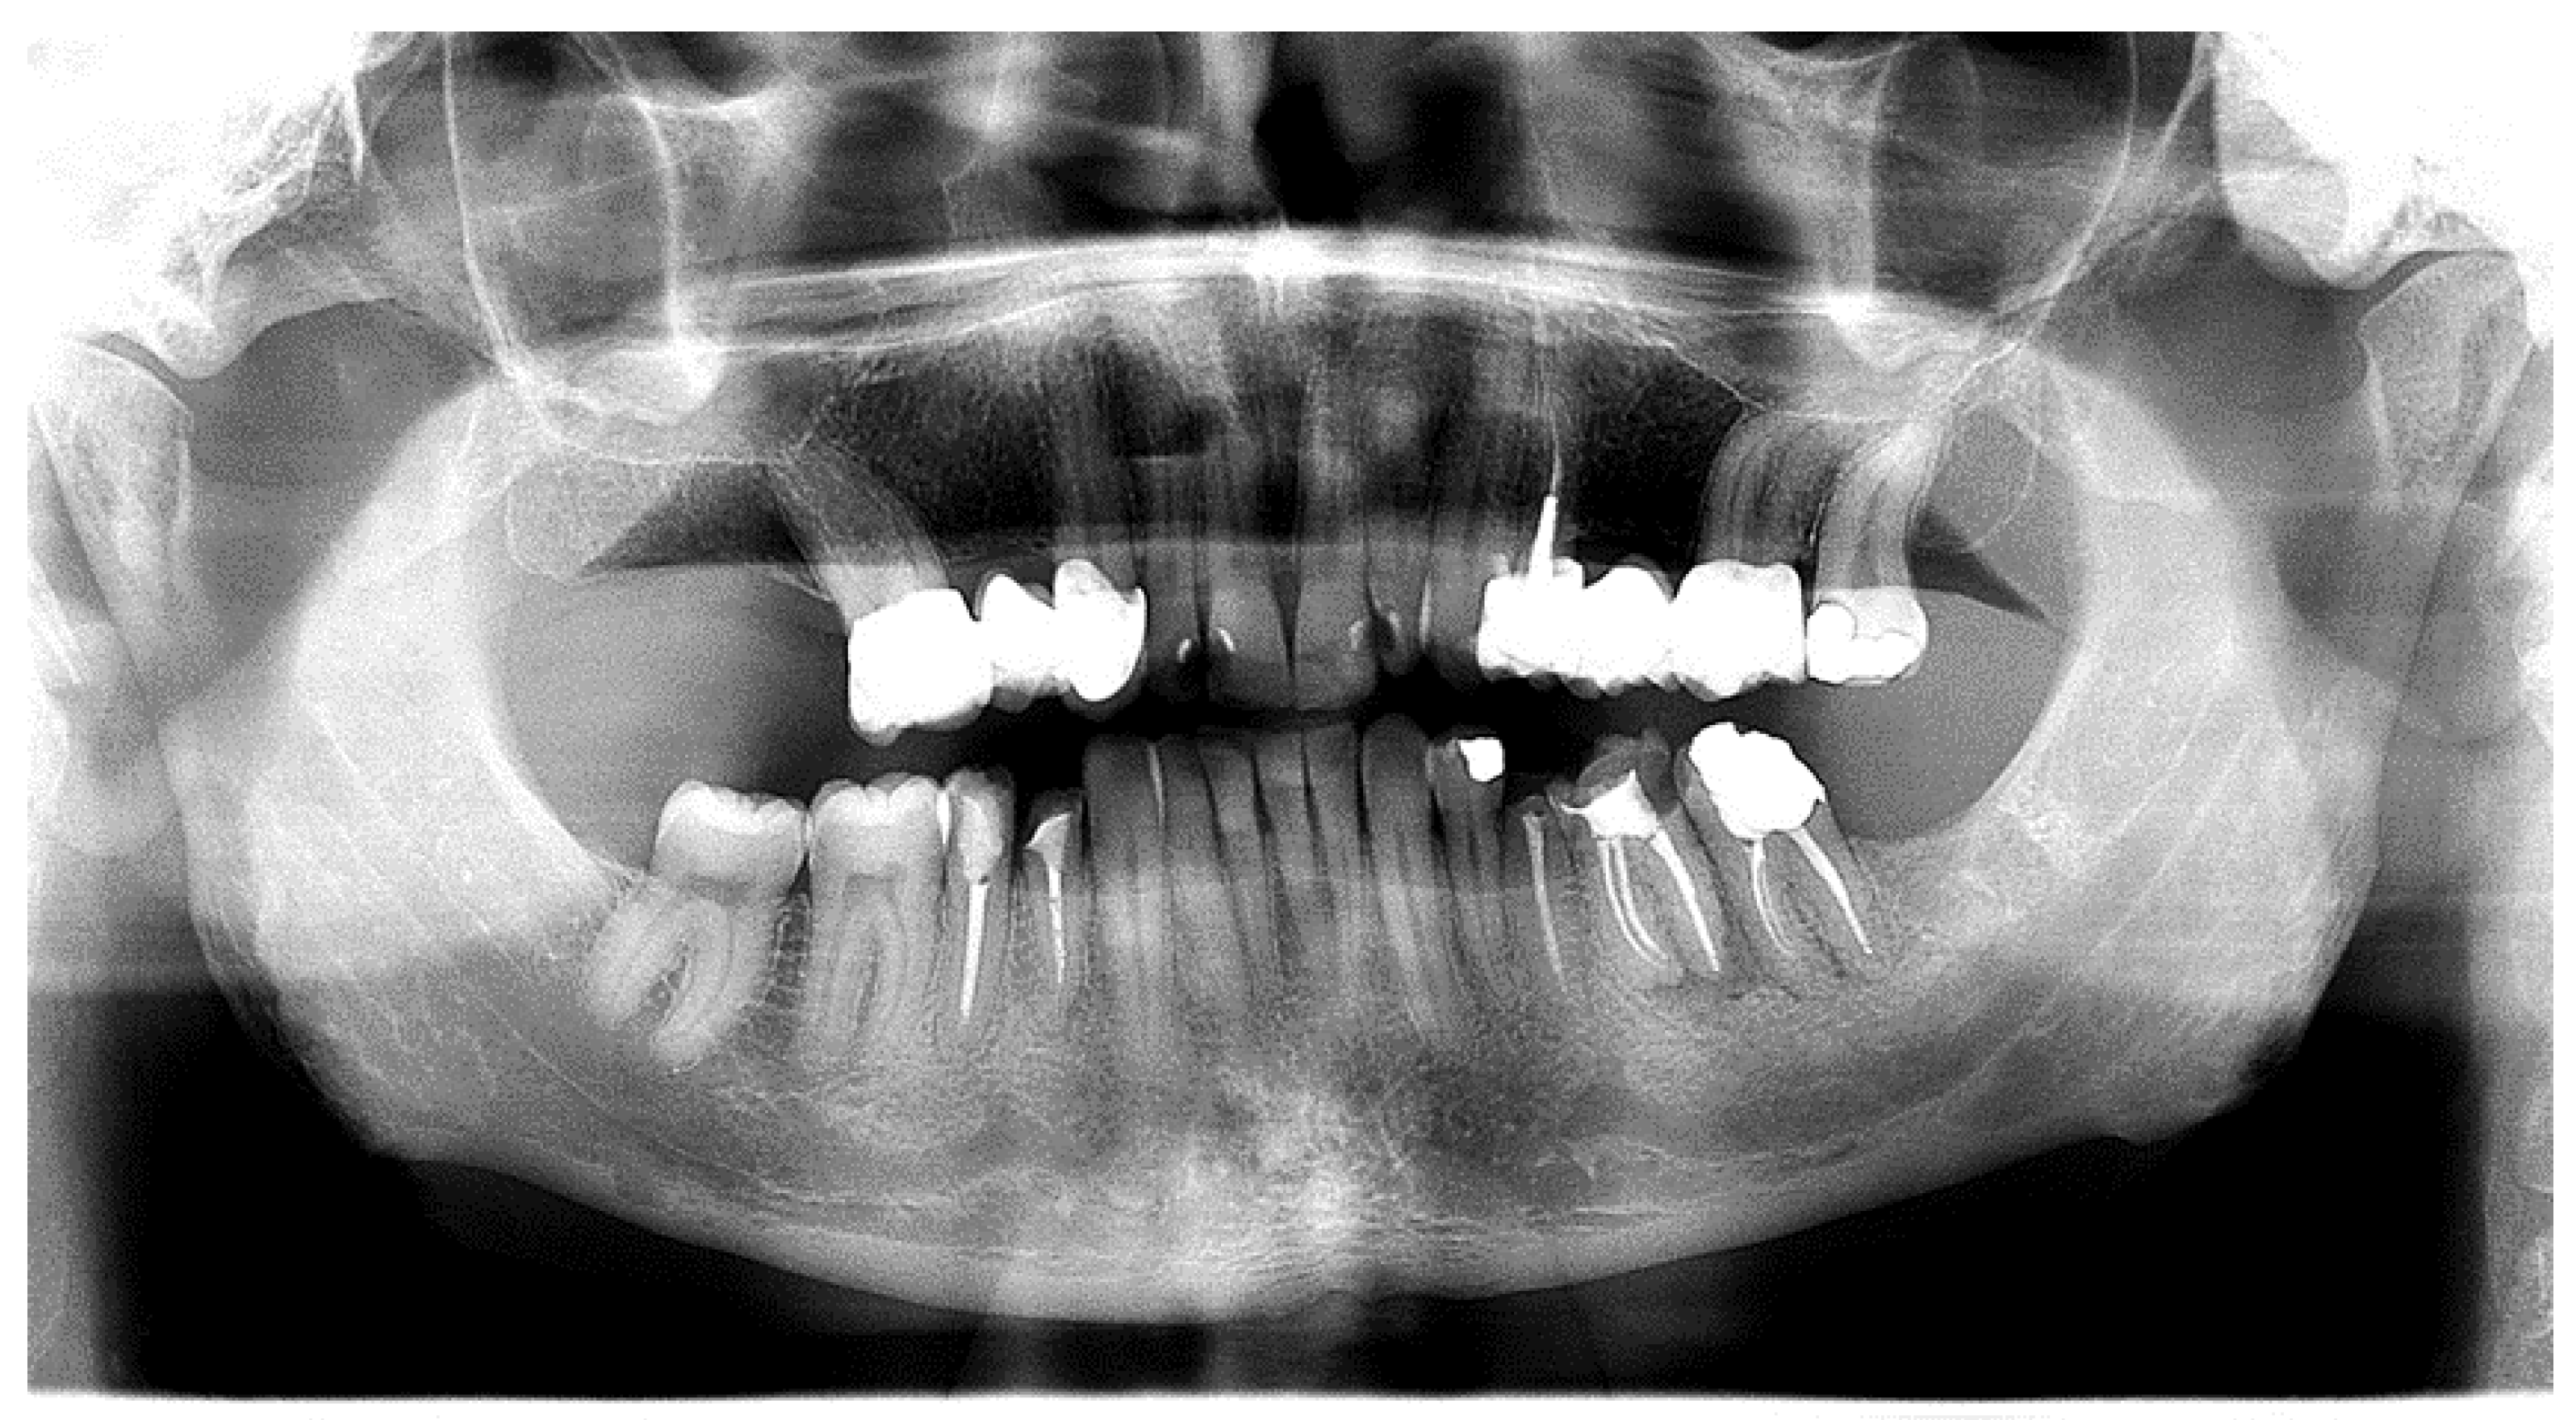

Oral Manifestations of Vitamin D Deficiency

Oral Manifestations of B-Complex Vitamin Deficiency

Oral Manifestations of Vitamin C Deficiency